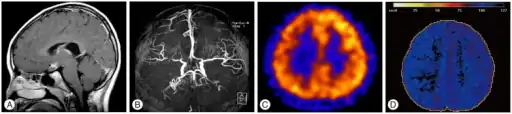

Right: healthy patient, for comparison.

Cerebral angiography is the gold standard of diagnosing moyamoya disease and its progression. According to Suzuki's system, it can be classified into six stages:[14]

Magnetic resonance angiography (MRA) is also useful in diagnosing the disease with good correlation with Suzuki's grading system.[14]

Often nuclear medicine studies such as SPECT (single photon emission computerized tomography) are used to demonstrate the decreased blood and oxygen supply to areas of the brain involved with moyamoya disease. Conventional angiography provides the conclusive diagnosis of moyamoya disease in most cases and should be performed before any surgical considerations.